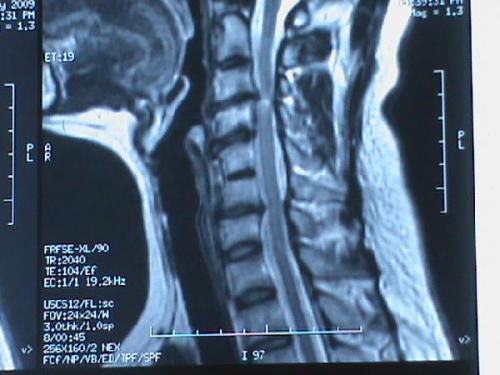

哪些人不能做颈椎牵引?

1.年老体迈,全身状态不佳者;

2.颈椎及邻近组织的肿瘤、结核或血管损伤性疾病者;

3.颈椎融合术后或内固定术后;

4.严重颈椎失稳或颈椎体骨折;

5.脊髓明显压迫者;

6.严重的骨质疏松患者;